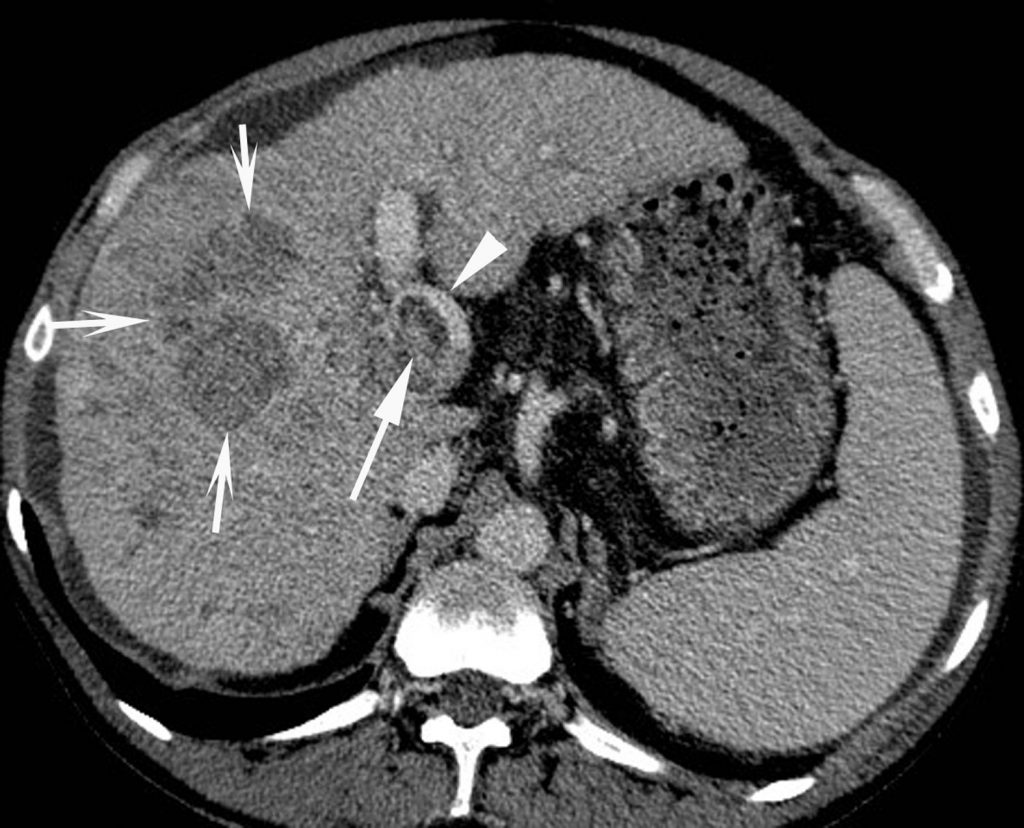

Cette tumeur a tendance à envahir la lumière de la veine porte (ou plus rarement des veines hépatiques ou des voies biliaires), ce qui est également très évocateur (figure 16.4).

Fig. 16.4. Coupe scanner : au temps tardif après injection de produit de contraste d’un CHC développé dans le foie droit visible sous la forme d’une tumeur hypodense en raison du lavage (flèches creuses).

Mise en évidence d’une extension tumorale (flèche) dans la lumière de la veine porte (tête de flèche). Le temps artériel non montré ici objectivait un rehaussement ; le diagnostic de CHC avec envahissement tumoral de la veine porte est donc établi.

Source : CERF, CNEBMN, 2022.